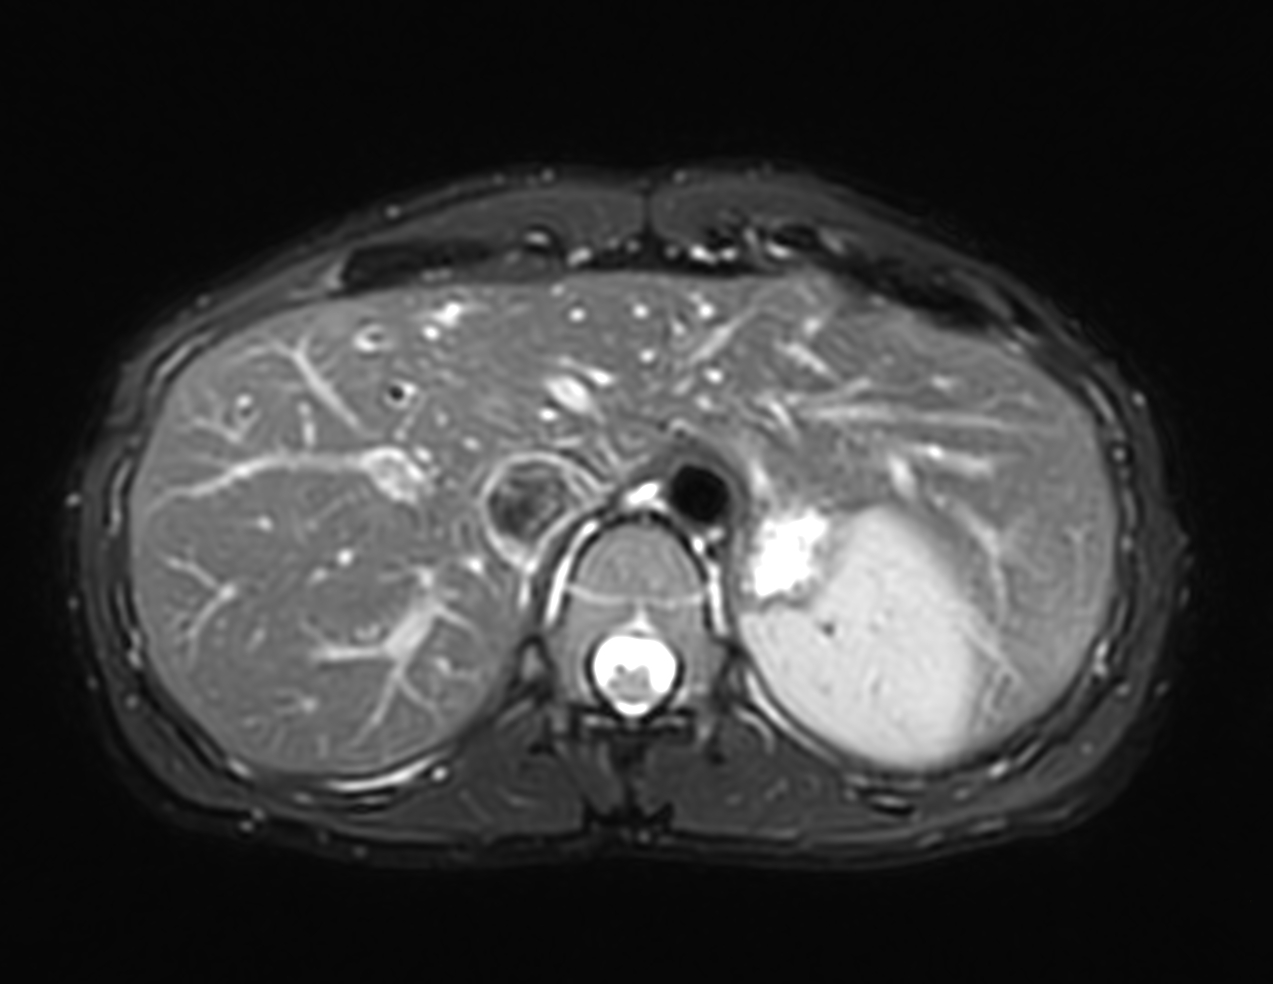

Axial MultiVane XD - T2w SPIR